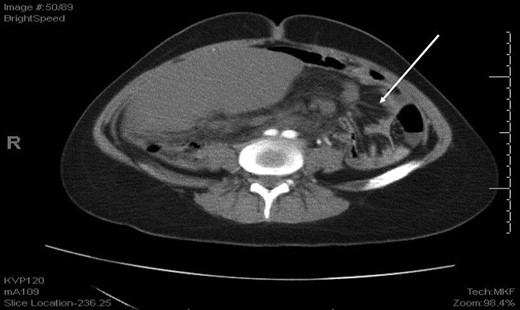

An axial CT shows dilated engorged mesenteric vessels (white arrow) indicating mesenteric varices.